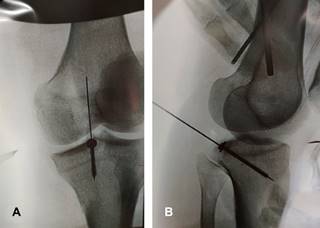

La fractura por avulsión del ligamento cruzado posterior (LCP) representa la lesión aislada más común del LCP (~ 50%), implicando la separación de la inserción tibial posterior del LCP en grados variables. Estos traumatismos se observan comúnmente en accidentes de motocicleta o automovilísticos (lesiones en Tableros de instrumentos) en los que se producen fuerzas de posteriorización contra la tibia en una rodilla flexionada. También se observan en individuos que saltan y aterrizan sobre un pie en flexión plantar mientras la rodilla está flexionada, en el contexto deportivo (esencialmente colocando la tibia bajo una fuerza de posteriorización). Se les clasifica en tipo I: cuando el fragmento óseo no está desplazado; tipo II: existe desplazamiento hacia arriba de la cara posterior del fragmento de hueso tibial avulsionado; y tipo III: cuando el fragmento óseo avulsionado está totalmente desplazado. Clínicamente existe signo del cajón posterior. Radiográficamente, en la placa lateral se identifica discontinuidad ósea en la superficie articular tibial posterior (Figura 1). En la resonancia magnética o la tomografía computarizada, se puede observar un fragmento de hueso fracturado unido al LCP retraído (Figura 2). El diagnóstico diferencial incluye desgarro del LCP. El tratamiento es la reinserción quirúrgica del fragmento avulsionado (Figura 3).